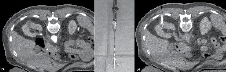

After adequate planning, 1% lidocaine is injected into the tract and an 18 gauge needle is left hubbed from the injection to determine whether it is in the vicinity of the mass. If properly positioned, this needle is exchanged for the RF probe after making a small incision. We prefer to use a 15-gauge RITA StarBurst probe (RITA Medical Systems, Mountain View, CA, USA) as the tine configuration permits visual confirmation that the entire tumor is enveloped. Figure 2 shows an example of how the tines appear deployed outside of the body and by CT scan. Under CT fluoroscopy guidance the probe is always inserted during a breath hold at end-expiration. The probe is advanced to puncture the tumor and then the tines are deployed rapidly. If inserted too slowly, the tines may not fully deploy. They should extend slightly past the tumor margin to ablate 0.5 cm beyond the mass. Near-perpendicular insertion of the probe on the mass is critical as it allows the greatest energy to be deposited at this deep margin where the region of highest blood flow is expected.

Figure 2. A) Before probe placement a CT scan is performed with IV contrast showing a 2.4 cm partially exophytic posterior ride sided tumor. B) The RITA StarBurst probe is shown with tines deployed. C) The configuration of the probe permits visual confirmation of coverage of the mass. Notice the ideal straight trajectory of the probe to the mass.